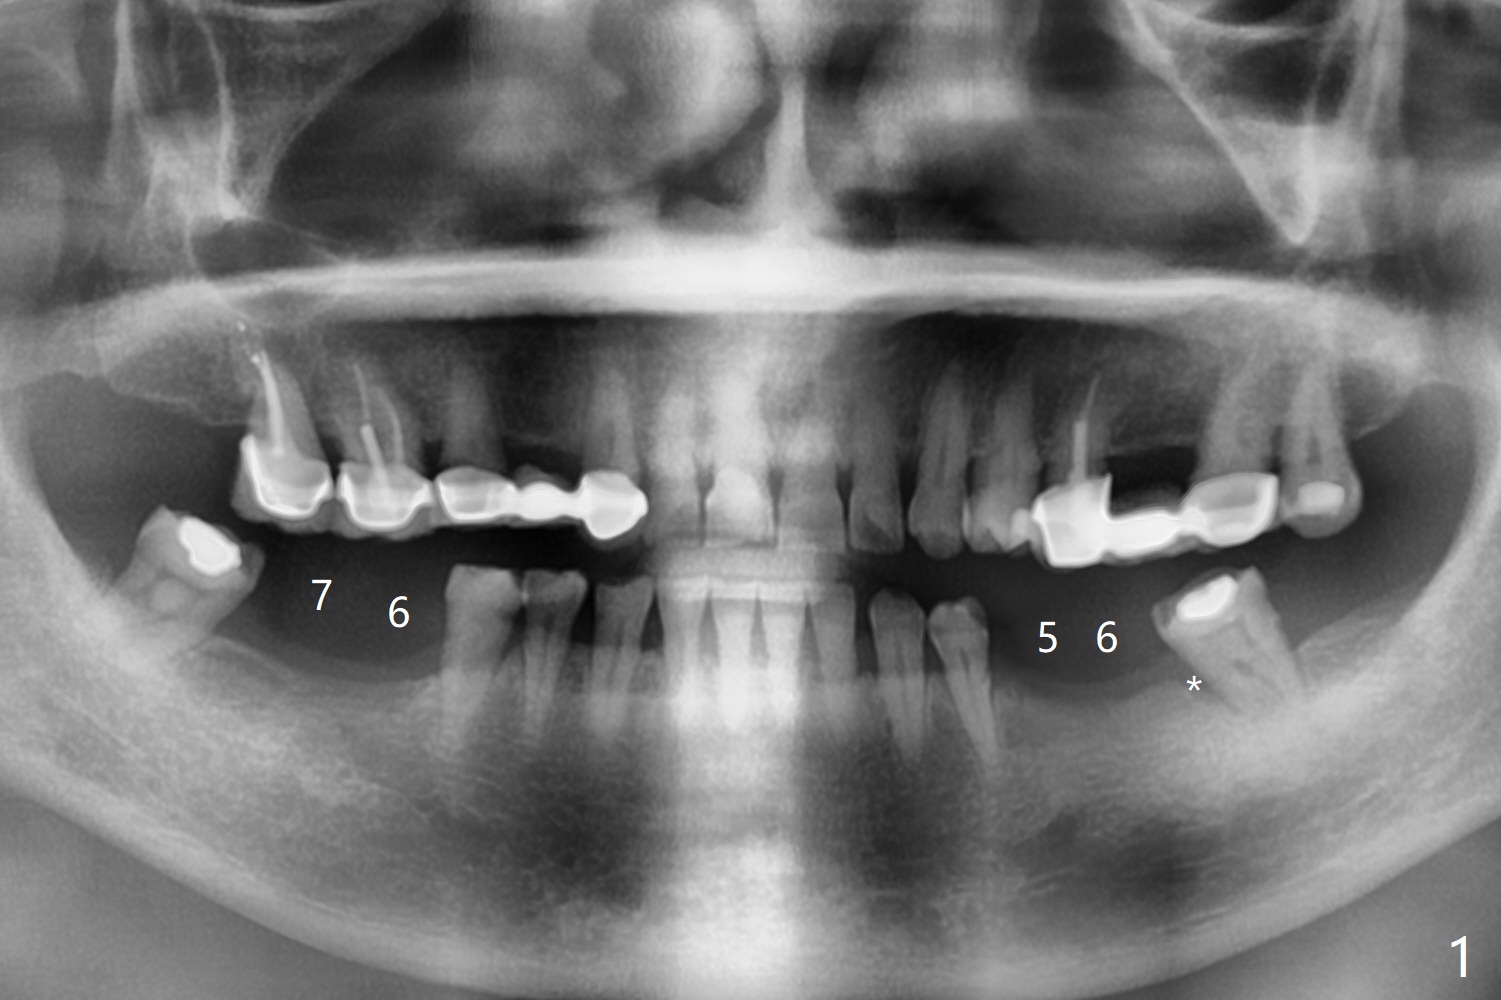

57岁女缺失四个下牙(图一),由于保险限制,先考虑左边种植(图二,三),主要问题是牙槽嵴狭窄(不过左上牙桥做的太长了,尤其是5,6(图一'),造成下面垂直距离缩短,修复困难。总之,她的牙齿显得短小)。牙槽嵴狭窄处理方法:切口,使用导板用bone trimmer和最细钻头(point drill或者2.2毫米)钻洞(图四:黑圆圈),到深度,然后用圆形骨锯在牙槽嵴顶部劈开(弯曲红线),必要时做三个垂直骨切口(图六),徒手利用旋转式骨扩张器,或者骨凿,推开颊侧骨板。也准备外科钻头(新的)。放置导板和钻头除去舌侧骨板,最后在5,6分别植入3.0 或者3.5毫米,4.0或者4.5毫米植体。如果初步稳定性好,即刻修复,主要防止7继续近中倾斜,必要时,7近中(图一*)植骨。抽血制备两个PRF膜和粘性骨块。